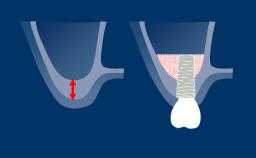

O uso de implantes dentários tornou-se um tratamento padrão em muitas situações clínicas. No entanto, para alcançar resultados funcionais e estéticos ideais, o clínico deve avaliar a complexidade e os riscos associados a uma terapia de implante antes de iniciar o tratamento. O sistema de classificação SAC diferencia entre tratamentos simples, avançados e complexos. A 2ª Edição totalmente revisada da Classificação SAC em Implantodontia foi atualizada para garantir consistência com a prática contemporânea de implantes. A nova versão do SAC Assessment Tool também está disponível aqui.

- discutir o gerenciamento de riscos em implantodontia

- descrever os determinantes da Classificação SAC

- descrever o processo usado para desenvolver uma classificação